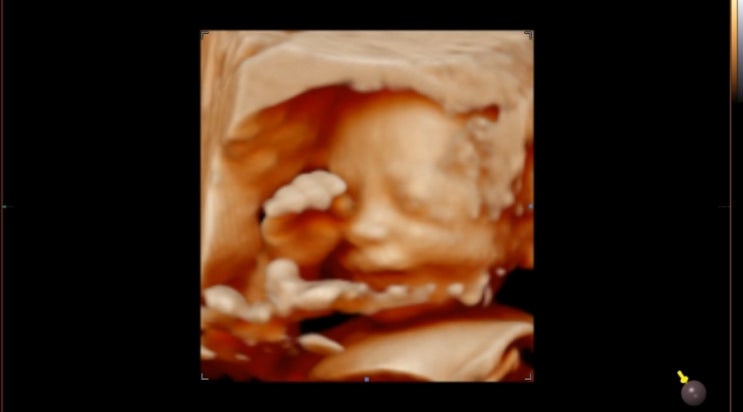

28주 입체초음파 비용 베이비페이스 할까 말까 고민이라면

어느 덧 28주..! 임신 말기에 접어들었다. 두둥... 24주쯤 정기 검진 갔을 때 선생님이 다음 검진일이 있는...